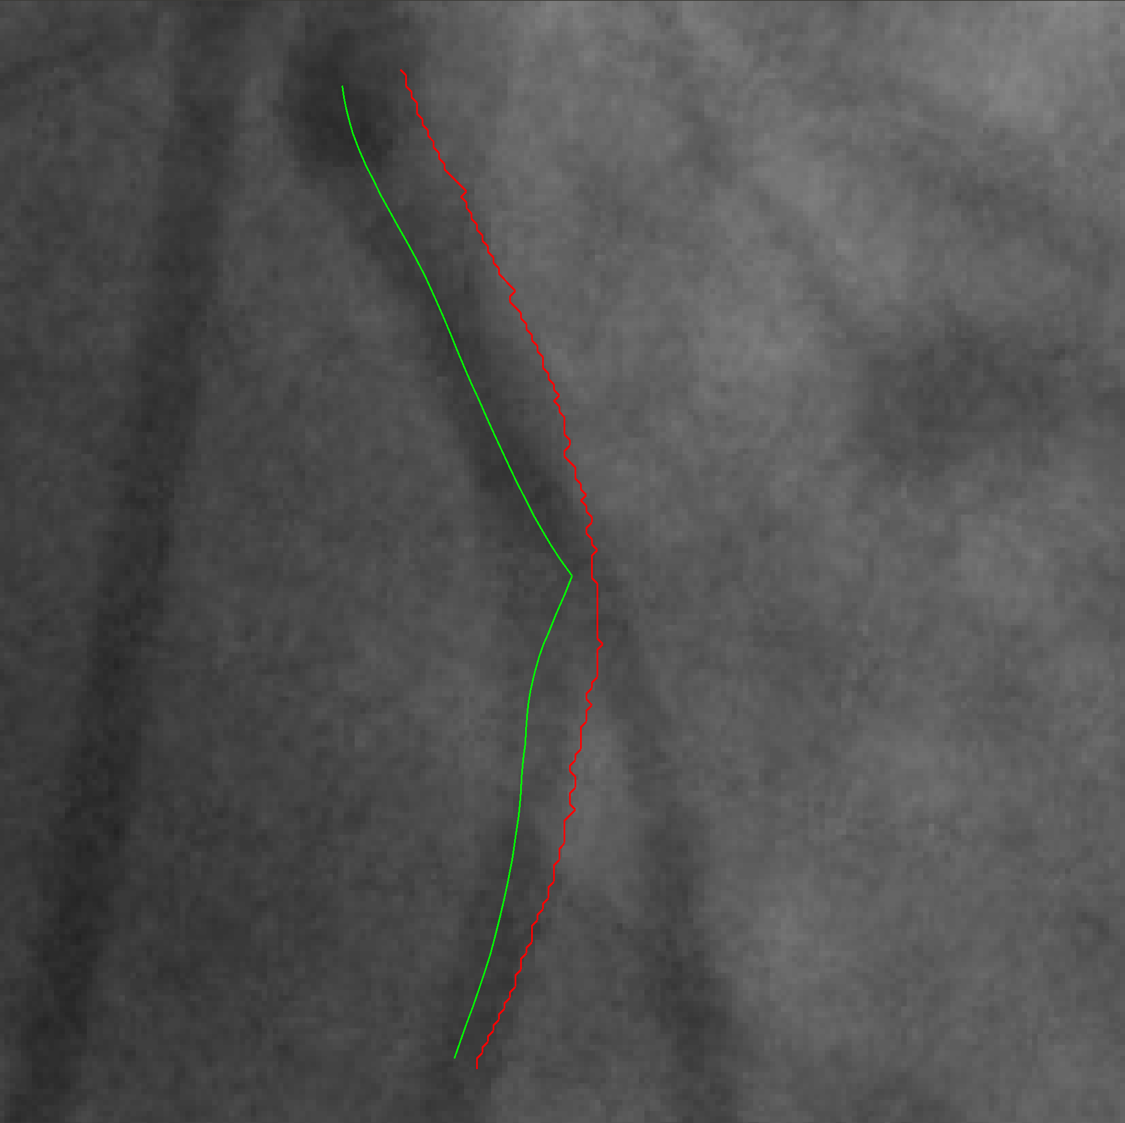

Refer to captionRefer to caption

Figure 2: VOIDD result: ground truth(in green) and vessel of intervention obtained from longest track(in red). In ground truth, the catheter is marked by the expert but not part of the tracked vessel because the guidewire tip is not detected when it is still inside the catheter. In this case, the vessel makes a very tight loop (blue arrow) in the bottom. In the tracking, we fail to detect this loop.

Sequences A1, B1, C1 and D1 in Table 1 show the efficacy of VOIDD algorithm to detect vessel-of-intervention during guidewire navigation in 4 patients and over 1513 images. In summary, VOIDD algorithm is able to correctly determine the location of tip in the vessel-of-intervention with an accuracy of around 88%92%percent88percent9288\%-92\%. The sequences A2, B2, C2 and D2 in the Table 1 portray the efficiency to identify navigation sequence over 690 images when guidewire tip is absent in the fluoroscopic images. The VOIDD algorithm is able to detect these sequences as sequence without guidewire tip with accuracy of 98%99%percent98percent9998\%-99\%. Analyzing the navigation sequence detection accuracy of VOIDD, we can use it to automatically detect the arrival of the guidewire tip. The parameters involved in various stages of the algorithme.g. tip candidate extraction or TAD were designed based on the physical properties of guidewire tip, permissible speed of advancement of guidewire. Current implementation runs in average 0.330.330.33 seconds for tracking on a Intel Core i7 cadenced at 2.802.802.80 GHz. Videos are available as supplementary material111https://voidd-miccai17.github.io/. Figure 2 shows the vessel of intervention obtained by the VOIDD algorithm and corresponding ground truth on left.